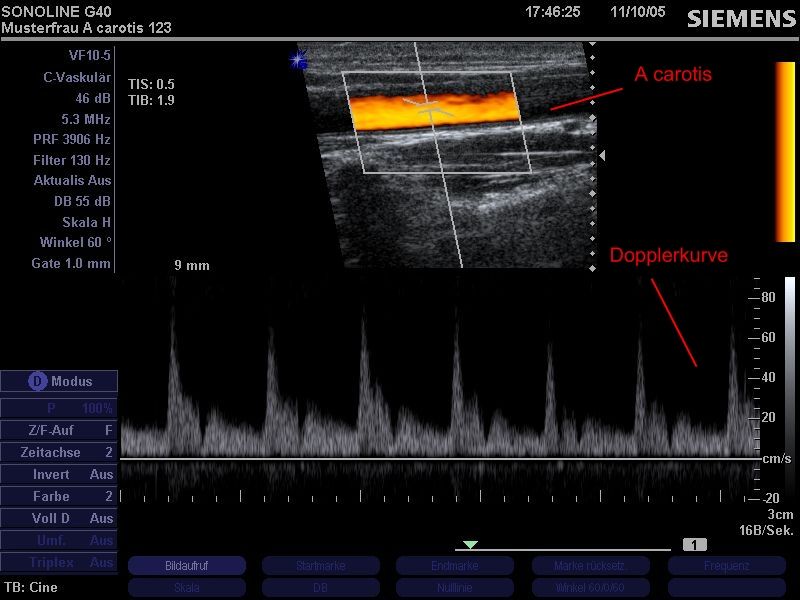

Sonographie der Halsgefäße (A.carotis). Die farbkodierte Duplexsonographie erlaubt eine Beurteilung der Durchblutungsverhältnisse, der Wandbeschaffenheit der Arterie sowie eine funktionelle Beurteilung der Flussverhältnisse (Dopplerkurve; im Bild unten). Damit können zuverlässige Aussagen über mögliche Gefäßverengungen bzw. Wandverkalkungen getroffen werden.